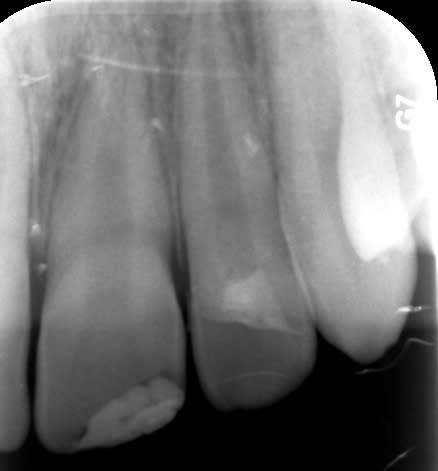

Enfant de 12 ans adressé par son dentiste le lendemain d'un trauma avec fracture de 21 et 22.

- 21 est une incisive mature mais jeune. Les cornes pulpaires sont très proéminentes et une fracture même d'apparence minime a donc une implication pulpaire directe. Il faut recouvrir en urgence le trait de fracture : ici par un CVIMAR (Fuji II LC). Une restauration par résine composite sera réalisée.

- 22 présente une exposition pulpaire ancienne de 20 heures. 20 heures donc que les germes buccaux contaminent directement la pulpe, heureusement jeune et donc avec un fort potentiel de défense.